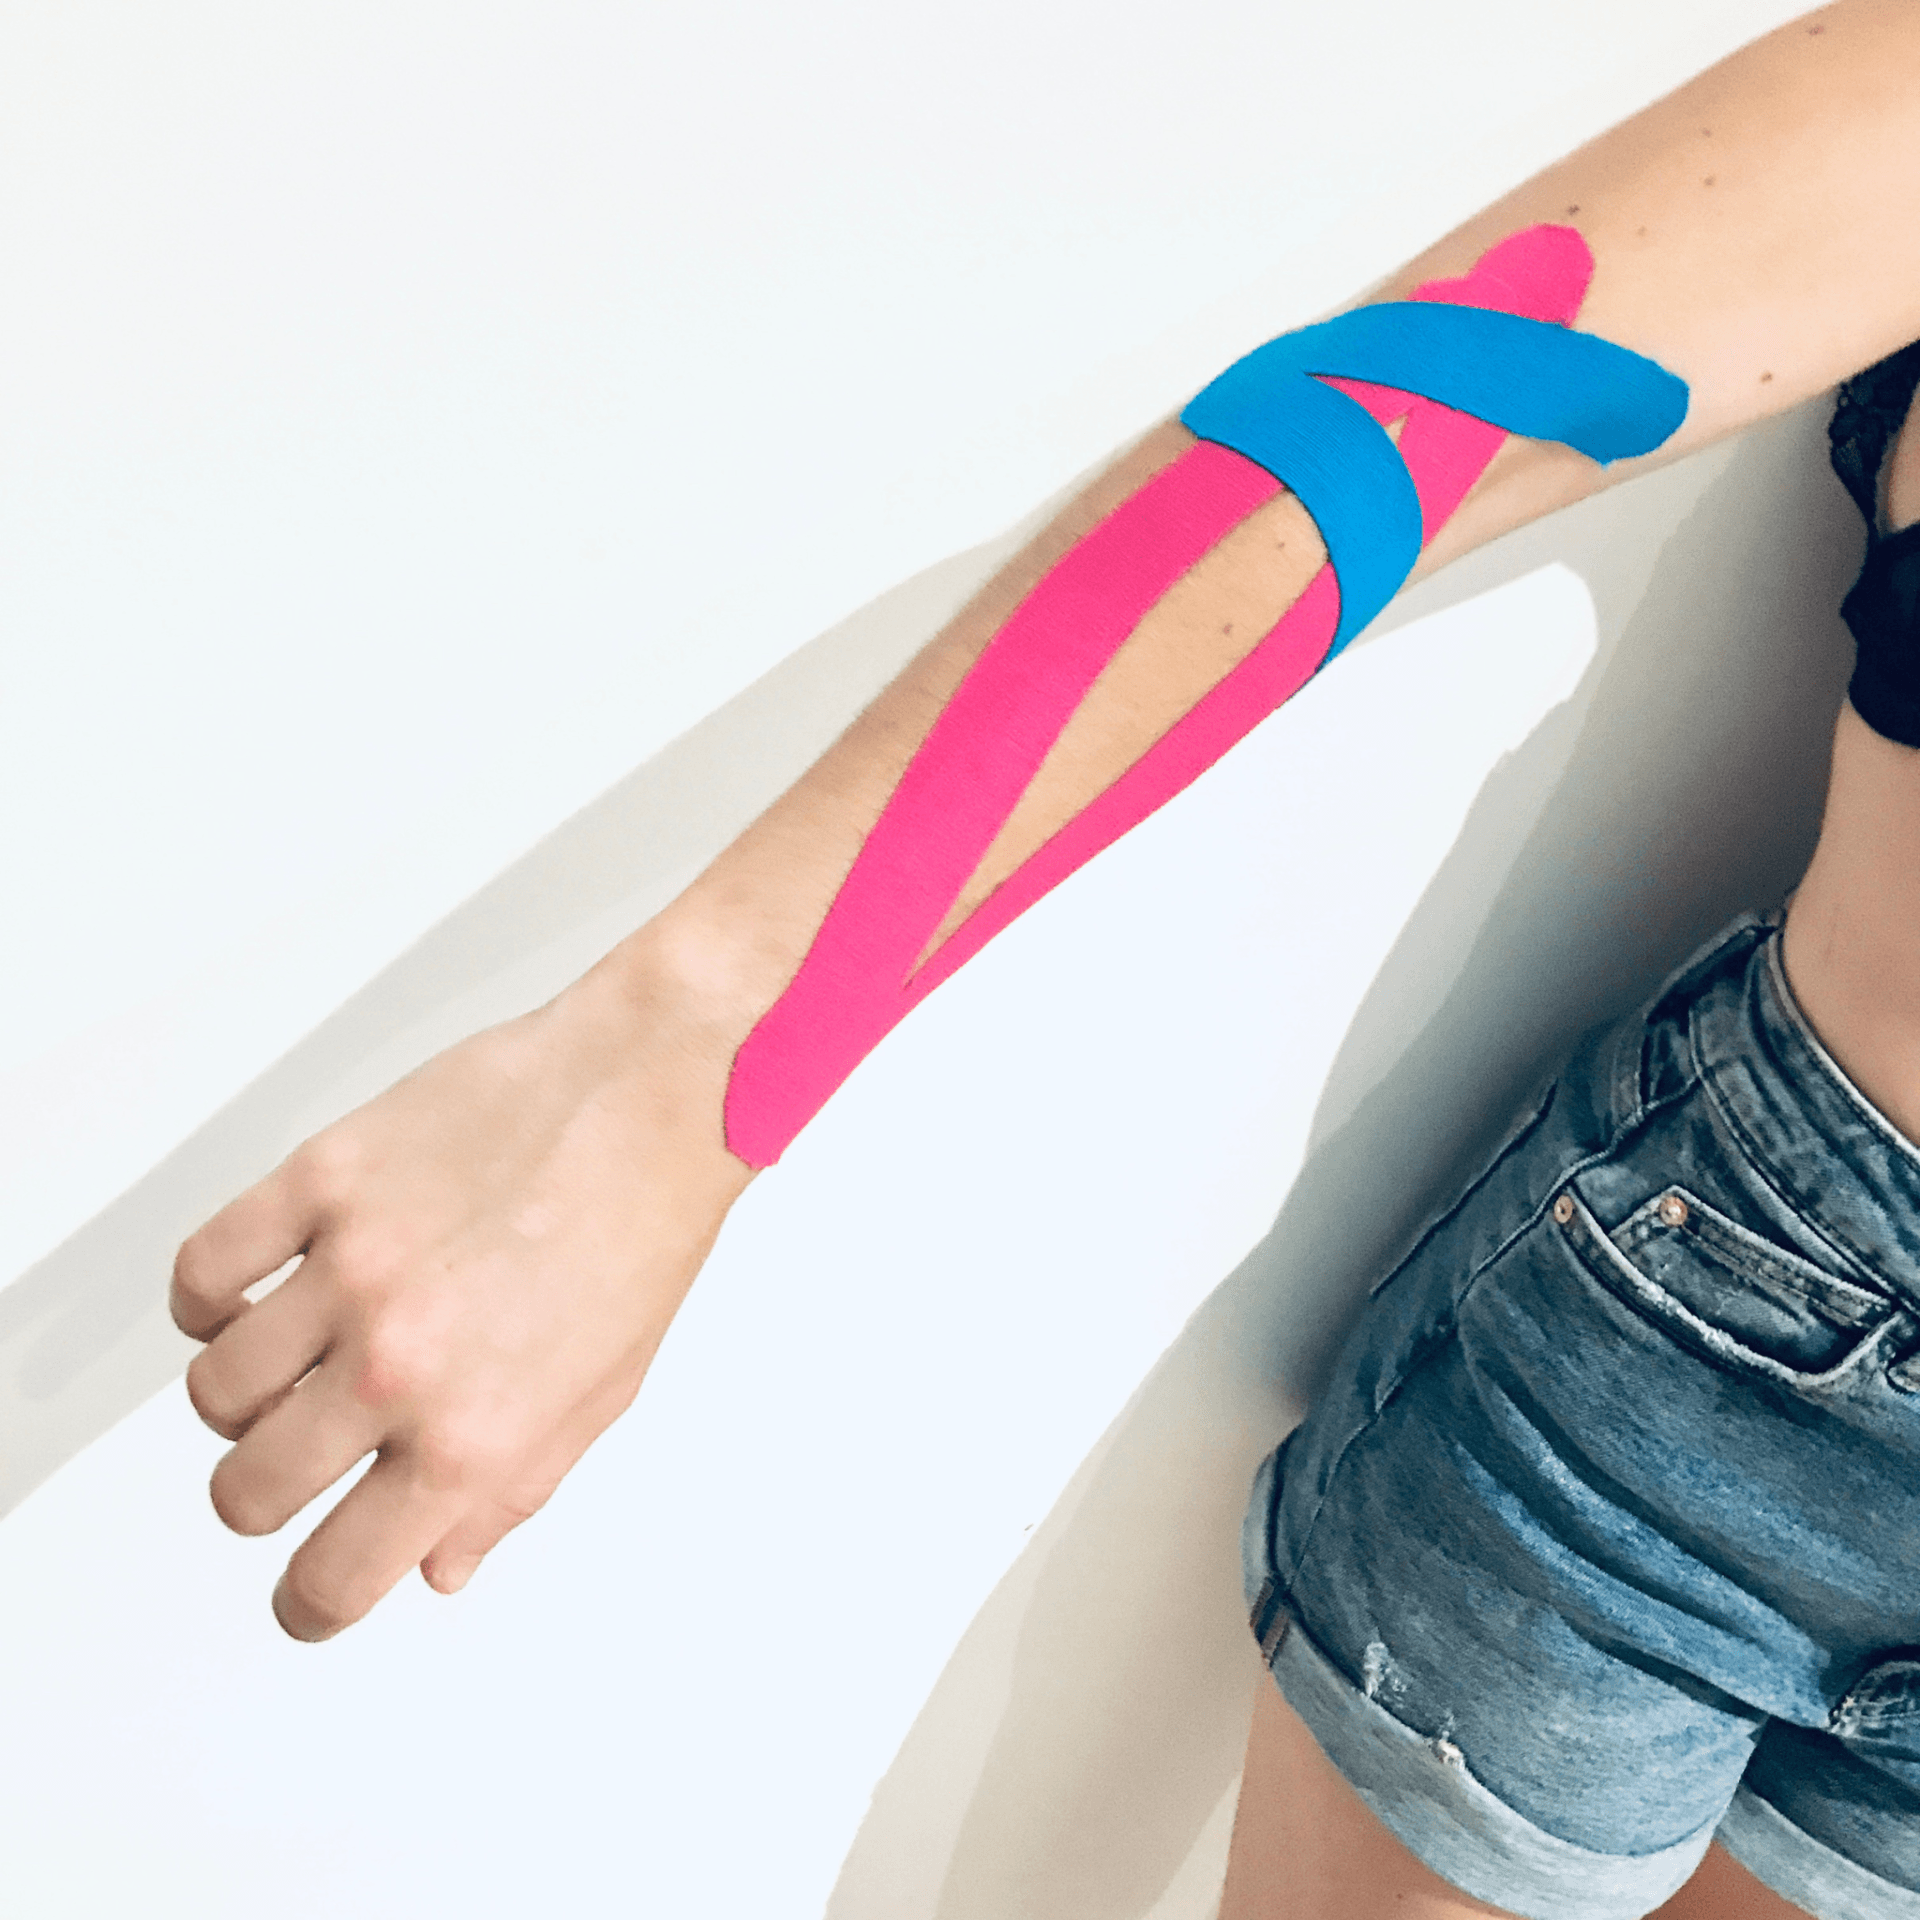

Respetando el proceso natural de recuperación de nuestro organismo el VENDAJE NEUROMUSCULAR facilia la función muscular normal, sin limitar la movilidad, evitando de este modo, el deterioro provocado por la inactividad, como son las atrofias, anquilosamientos, adherencias, pérdida de la propiocepción, etc.